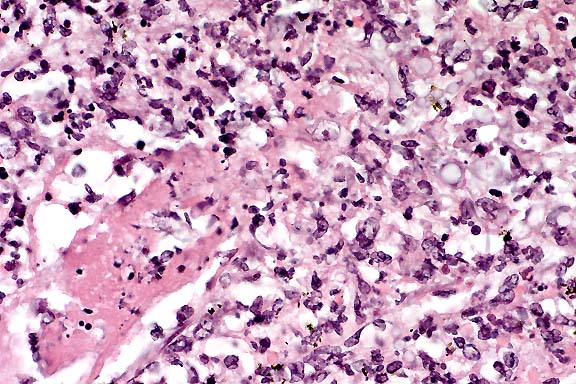

40x

Obj.

- Case 4-1. Liver. Large portal vein to right contains

sloughing cells with basophilic intranuclear inclusions. Similar

intranuclear inclusions are in most degenerating hepatocytes

as well.

- AFIP Diagnosis: Liver: Hepatocellular degeneration

and necrosis, diffuse, with mild multifocal acute hepatitis and

vasculitis, numerous hepatocellular intranuclear inclusion bodies,

and rare endothelial intranuclear inclusion bodies, striped skunk

(Mephitis mephitis), mustelid.